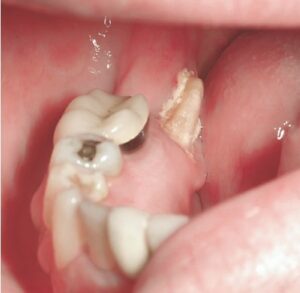

- شلوغی دندانی: دندانها به خاطر کمبود جا روی هم قرار میگیرند

- کراسبایت: دندانهای عقبی فک بالا به فک پایین منتقل میشوند

زمانی که بحث درمان تنگی بالا مطرح میشود تنها به فکر بازگرداندن زیبایی نیستیم، بلکه در غیر اینصورت مجموعهای از مشکلات عملکردی ممکن است فرد را تهدید کند. برای مثال از نظر دندانی، کراس بایت و تنگی فک بالا ساییدگی ناهموار دندانها و جویدن سختتر را میکند و در نتیجه هضم را مختل میکند. درمان شلوغی دندان بیشتر نیاز به وسیع کردن اولیه دارد، به همین دلیل ارتودنسی به تنهایی جواب نمیدهد.